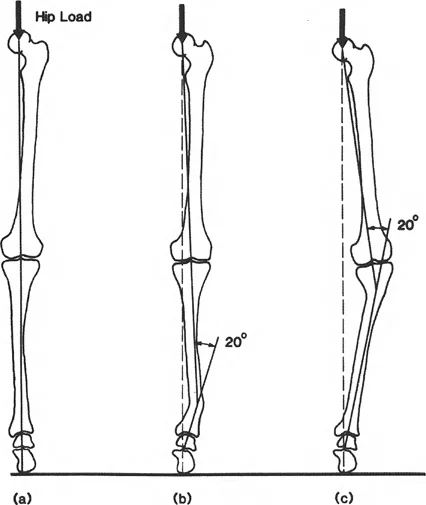

Central to understanding lower limb deformity is the concept of the weight-bearing axis, universally termed the mechanical axis.

Pioneered by the visionary biomechanist Friedrich Pauwels in the 1980s, the mechanical axis of the lower extremity is depicted as a straight line passing from the center of the ankle to the center of the hip. This line represents the path of transmission of the load-bearing force relative to the lower extremity during a static, two-legged stance.

Any deformity in the coronal plane that alters the alignment of the joints of the lower extremity disturbs this load-bearing axis. When the load-bearing axis passes medial or lateral to the center of the knee, it creates a moment arm. This moment arm acts as a lever, exponentially increasing the force transmitted across either the medial or lateral tibiofemoral compartment.

The Mechanical Axis Deviation is the foundational metric of lower extremity alignment. On a standing 51-inch anteroposterior radiograph, the mechanical axis of the lower extremity is a line drawn from the center of the femoral head to the center of the tibial plafond.

In a normally aligned limb, this line passes slightly medial to the exact center of the knee joint, typically 8 to 10 millimeters medial to the midpoint of the tibial plateau.

When the mechanical axis line deviates further medially, the patient has a varus deformity, and the MAD is measured in millimeters medial to the center of the knee. When the line deviates laterally, the patient has a valgus deformity, and the MAD is measured in millimeters lateral to the center. Quantifying the MAD is the first step in determining whether a clinically significant deformity exists that warrants surgical intervention.